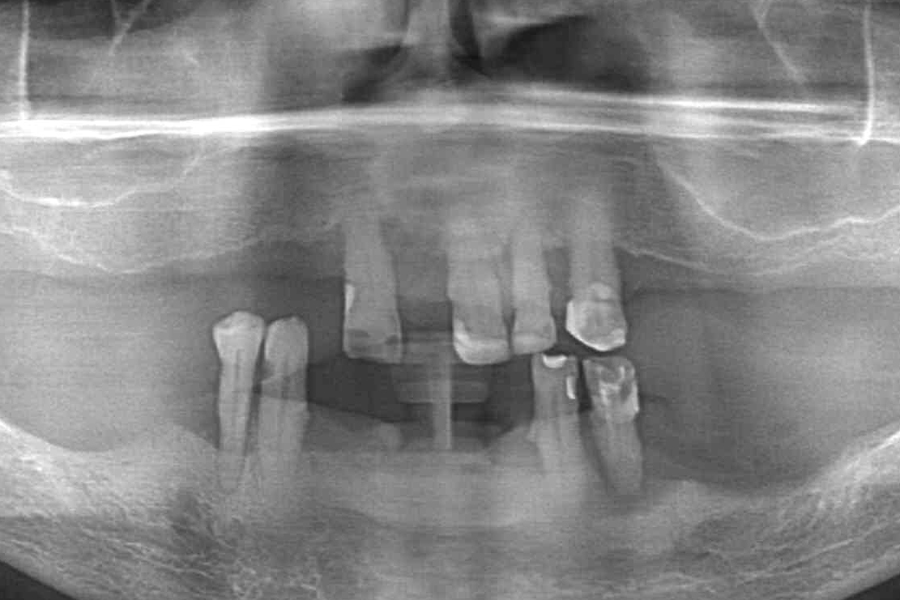

Diagnostyka radiologiczna - ocena statusu tkanek twardych i miękkich w obu łukach

Diagnostyka radiologiczna – ocena statusu tkanek twardych i miękkich w obu łukach

Stan wyjściowy - bez protez, liczne braki zębowe i po 2 nierokujące zęby w szczęce i żuchwie

Stan wyjściowy – bez protez, liczne braki zębowe i po 2 nierokujące zęby w szczęce i żuchwie